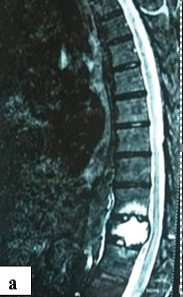

A Vertebral Fracture During Cardioversion for Atrial Fibrillation: A Case Report and Revision of the Literature

Matteo Spadini , Michele Ciabatti , Matteo Olivieri , Leonardo Bolognese , Patrizio Caldora

………………………………p.173-177